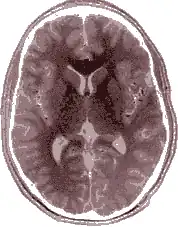

Einzelbild einer Magnetresonanz- tomographie eines menschlichen Gehirns; animierte Version mehrerer transversaler Schnittebenen -

- Auslöschungs- und Verzerrungsartefakte (durch lokale Magnetfeldinhomogenitäten), sog. Suszeptibilitätsartefakte (diese können aber auch ausgenutzt werden, um z. B. Blutungen im Gehirn zu diagnostizieren)